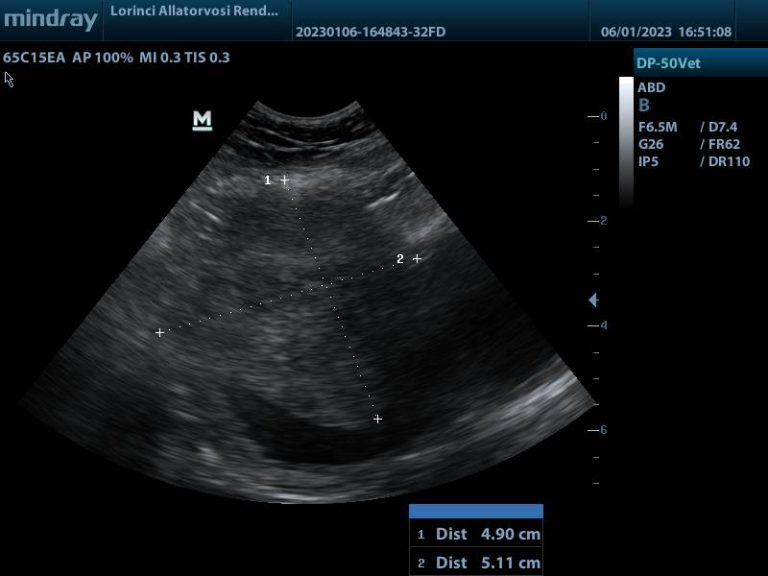

Húgyhólyag nagy részét kitöltő daganat

Megvastagodott hólyagfal és calcificatio

Bal vesemedence és urether tágulat

A hasi ultrahangvizsgálat során, telt hólyag mellett lehetőség van többek között a falszerkezet és falvastagság elbírálására. Az ép húgyhólyag fala kutyákban 3 mm-nél, macskákban 2 mm-nél nem vastagabb, sima felszínű, egyenletes. A falvastagságot kissé befolyásolja a hólyag teltsége, minél több vizelet van a hólyagban, annál jobban ellaposodik.

Ha a hólyag fala egyenetlen, megvastagodott, vagy massza türemkedik a hólyag üregébe – különösen a trigonum tájékán -, az aggodalomra adhat okot. Az ultrahang azonban önmagában nem különíti el a daganatos – és gyulladás miatti elváltozásokat, viszont a citológiával, illetve szövettani vizsgálattal együtt hasznos és fontos vizsgáló módszer.